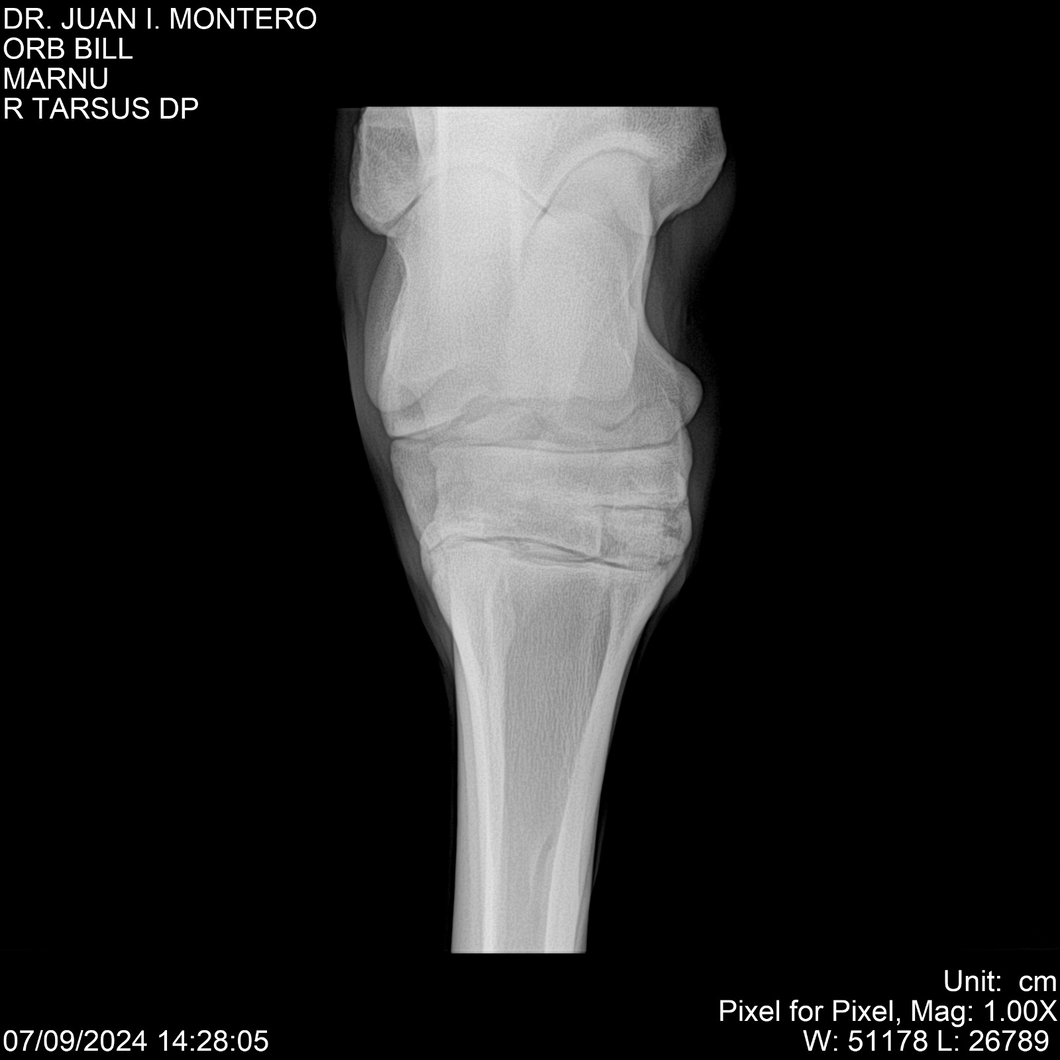

LOTE 7, ORB BILL 🔥 🔥 🔥 Lote Anterior Volver al remate Lote Siguiente Ficha Contacto Montevideo - Ficha del Lote Identificador: #282523 Categoría: Yeguarizos Montevideo - 83 Visualizaciones ClicData Contacto Empresa: Abelenda N. R., Walter Hugo Nombre*: Teléfono* : E-mail* : Mensaje Enviar Registrese gratis Este contenido Exclusivo está disponible sólo para usuarios registrados Ingresar